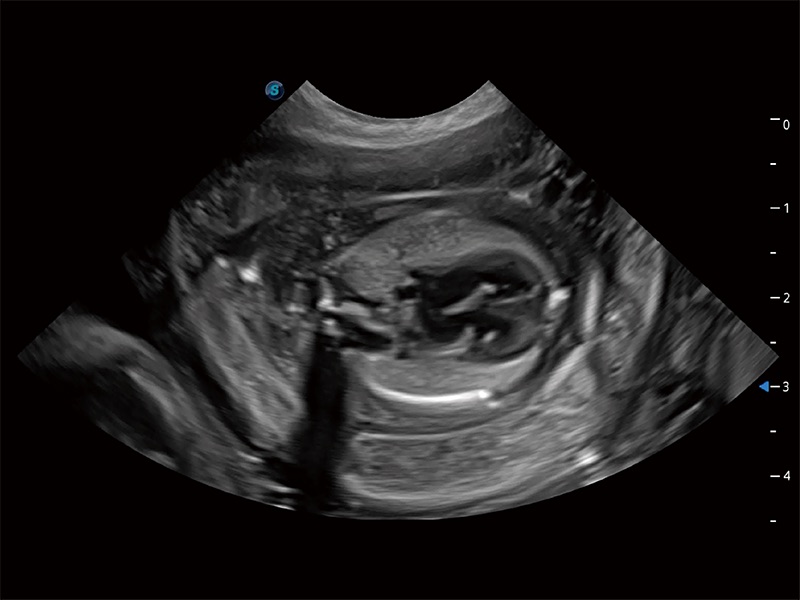

动物是人类最亲密的朋友和最值得信赖的伙伴。哈哈体育官网也一直致力于探索动物专用的超声影像解决方案。全新推出的ProPet系列,是哈哈体育官网在动物超声影像智能化、专业化、精准化的一次跨越式革新。动物不能用言语来表述自己的不适,通过超声影像,ProPet系列搭建了动物医生与不同物种沟通的“桥梁”,为动物医生注入了“治愈之力”。 ProPet 80 是哈哈体育官网匠心打造的一款高端动物专用彩超,采用性能卓越的全新硬件架构,极大提升超声系统的运行效率和数据处理能力,帮助动物医生从容应对日益增多的挑战性病例和日益多样化的临床需求。

高性能和先进的临床应用工具可以为动物医生提供临床信心。ProPet 80 搭载了先进的腹部和浅表应用工具,帮助医生在日常临床实践中发挥前所未有的作用。

ProPet 80 专为动物医生设计,对不同的动物体型和生理结构作出了针对性的优化。通过动物影像专用软件,可满足个性化的应用需求,帮助动物医生获得更精确的诊断数据。